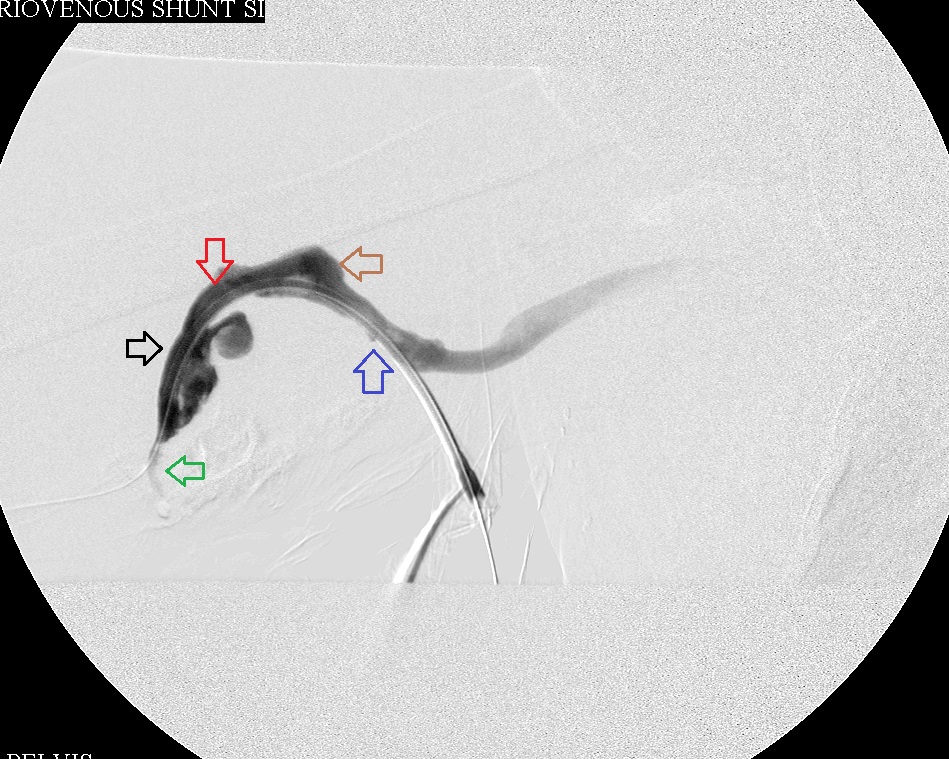

After dilating middle and distal stenoses

Right brachial venogram during intervention: Dilated 2nd and 3rd stenoses; juxtanastomotic stenosis was treated, but image not shown.